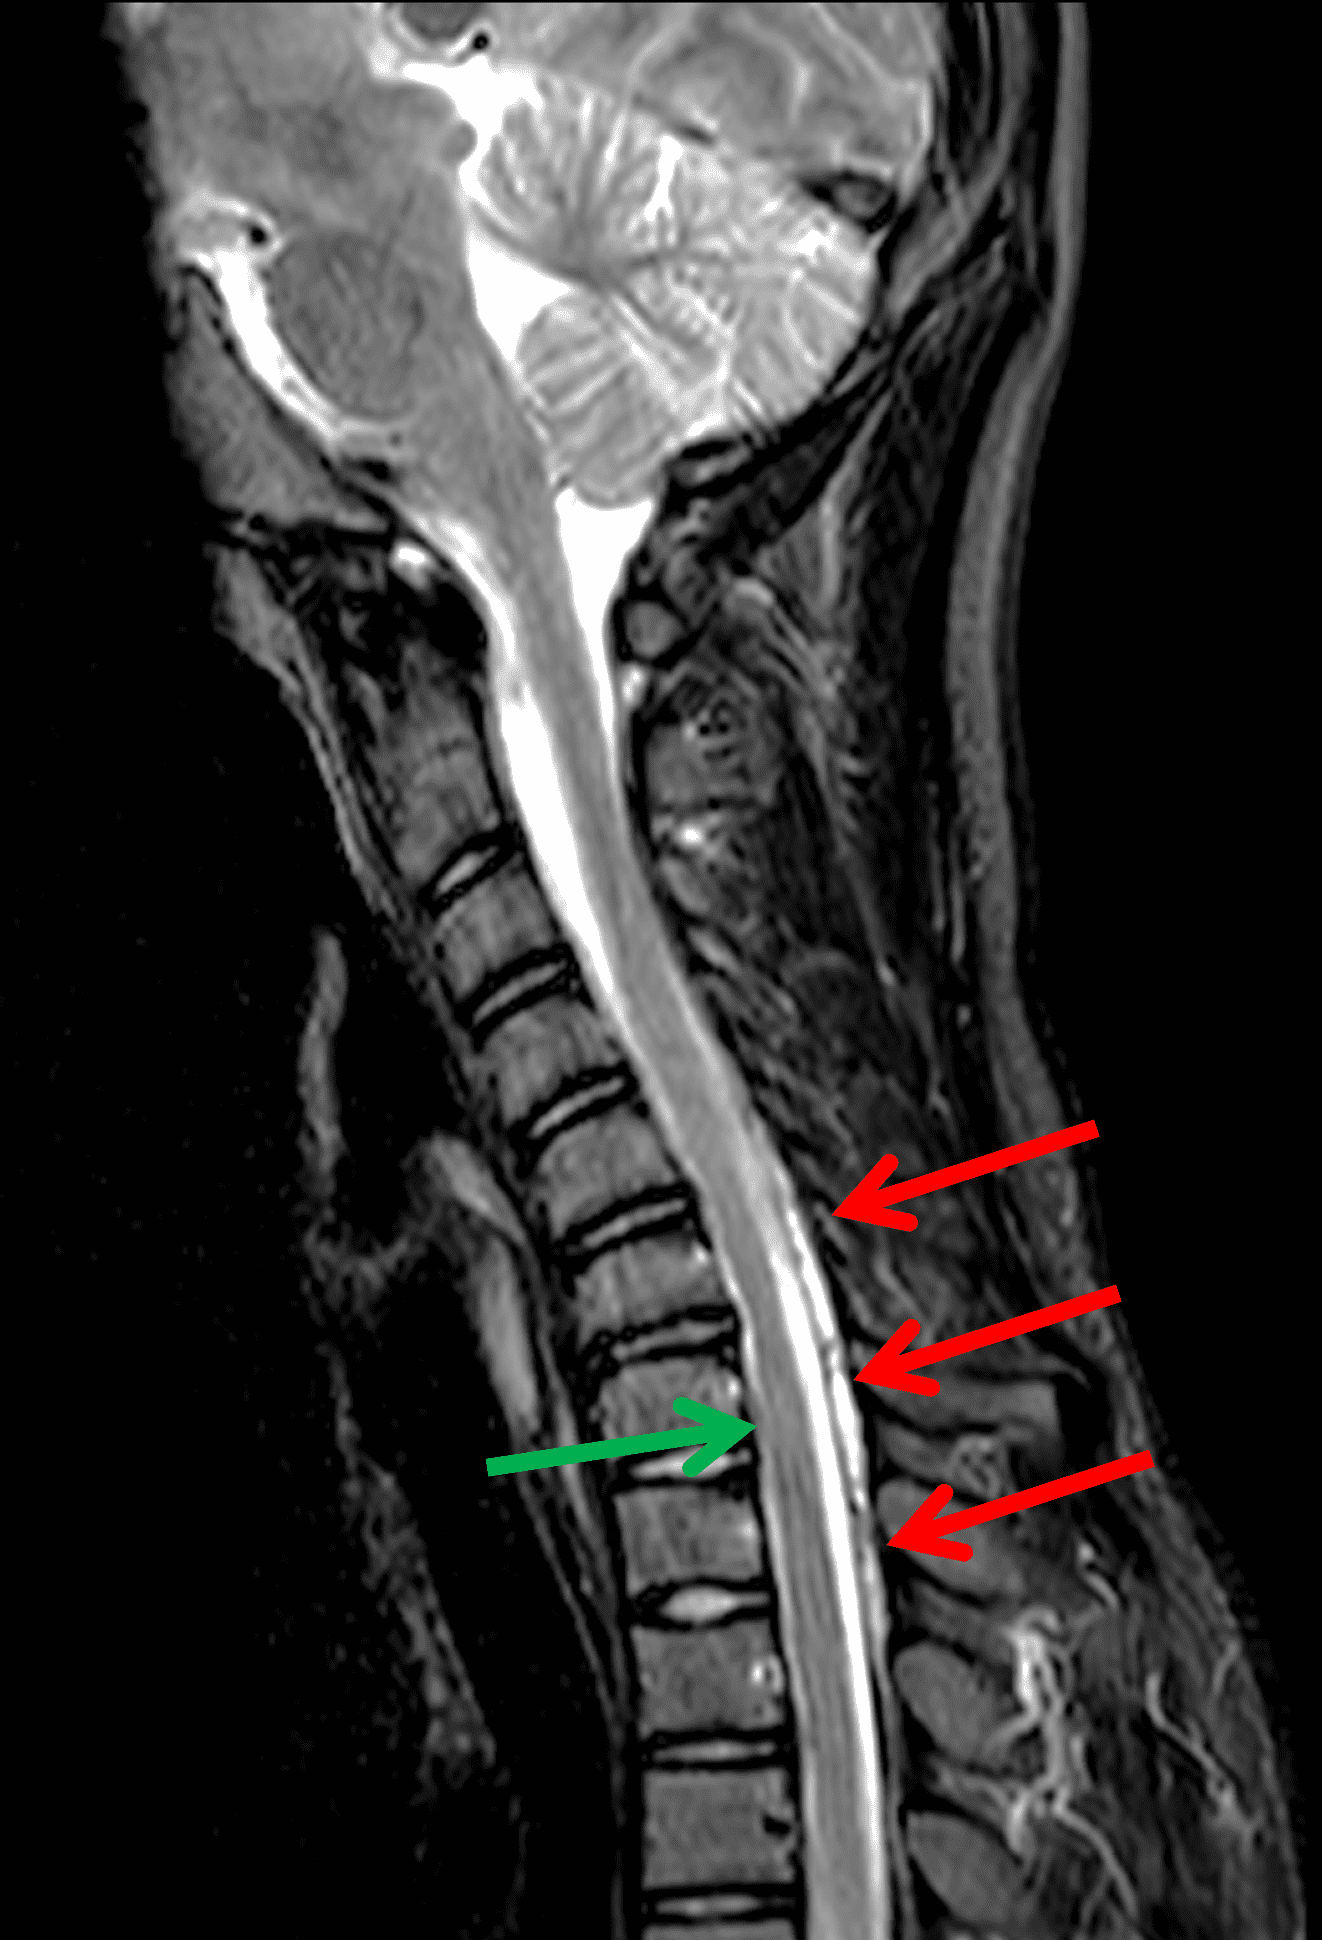

Figure 2: Neutral images of the cervical spine. Sagittal (2A) T2-weighted, (2B) T1-weighted, and (2C) STIR images show mild kyphosis, an enlarged posterior epidural space with loss of attachment of the dura (red arrows), and cord atrophy at the C6 level (yellow arrow). Subtle cord hyperintensity on the water sensitive images at the C7 level (green arrows) likely represents gliosis. (2D) Axial T2-weighted image shows enlargement of the posterior epidural space, right greater than left (red arrows). (2E) Axial T1-weighted image shows an enlarged posterior epidural space (red arrows) and cord atrophy, more severe on the right (yellow arrow).